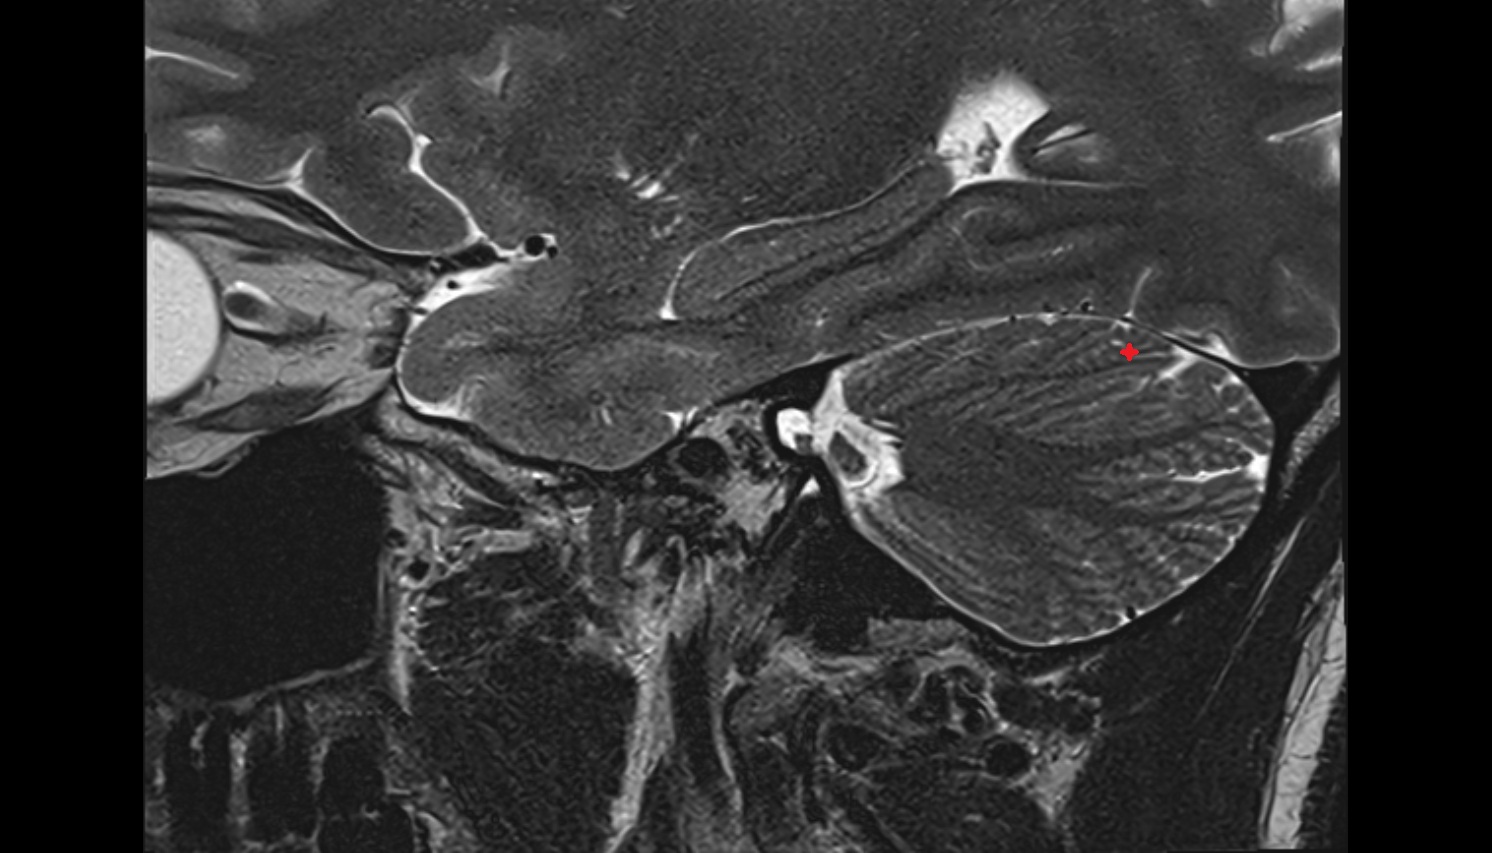

- Temporomandibular joint

- Articular disc of temporomandibular joint

- Articular eminence

- Mandibular condyle

- Mandibular fossa

- Superior head of lateral pterygoid muscle

- Inferior head of lateral pterygoid muscle

- Lateral pterygoid muscle

- Masseter muscle

- Temporalis muscle